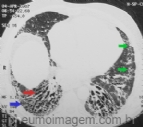

DESTAQUES DO ERS2016: FIBROSE PULMONAR IDIOPÁTICA ASSOCIADA AO ENFISEMA PULMONAR

A presença de mais de 15% de enfisema na TC de tórax impacta a variação da CVF no ano seguinte e isso pode ser um critério diagnóstico para a síndrome de associação entre FPI e enfisema. Múltiplos cistos grandes, diferentes do padrão em fav...